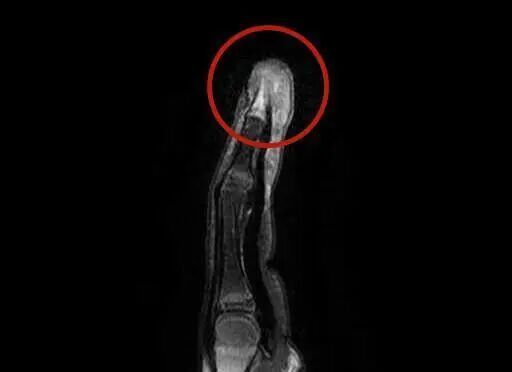

这下妈妈慌了神,连忙带小雨来到杭州市临平区妇幼保健院,小儿外科主任吴红军仔细查看了小雨的情况,结合检查结果,诊断为“脓性指头炎,立即为小雨做了手指脓肿切开引流手术,并收住入院静脉输液抗感染治疗。而更令人揪心的是,核磁共振显示小雨的指骨已经出现了吸收破坏,这意味着感染已经侵袭到骨骼,发展为更加严重的“骨髓炎”!

图片

放射检查:脓性指头炎/医院供图